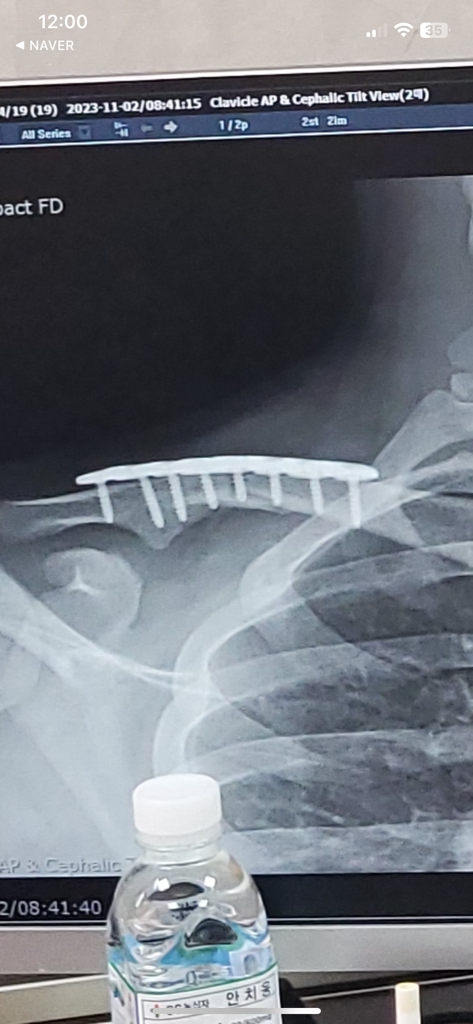

혹시 뼈에 골진이 생기고 있는지 알 수 있을까요..?

오늘로 2개월 차인데 의사선생님께서 아직 안 붙었다고 하셔서 불안한 마음에 작성해봅니다...(사진이라 구별이 잘 안될 수 있을거 같습니다ㅠㅠ)

보통 부러진 부분 주변으로 희끄무레한 덩어리가 형성됩니다

가골이라고 하는데요

아직 형성이 되지 않았네요

시간이 걸리나 봅니다

• 엑스레이 사진 한 장을 통해서 뼈에 골진이 생기고 있는지 여부를 판단하는 것은 가능하지 않습니다. 유감스럽지만 구체적으로 파악할 수 없습니다.